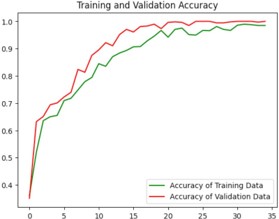

Model training

Python code has been used for the training and testing process. The code contains several libraries such as tensorflow, numpy, matplotlib, keras which is a higher-level neural networks API that comes integrated with tensorflow [1]. The loading of the training and test datasets is done using tf.keras.preprocessing.image_dataset_from_directory(). A neural network model with multiple layers is created using keras that contains convolutional, Max-pooling, Dropout and Dense layers. Sparse categorical cross-entropy loss function and Adam optimizer are used to build the model. The training process is run for 35 epochs as shown in figure 8. The loss and accuracy gained is plotted and the visualization of the test images and predictions are made which was displayed in figure9. Finally, the trained model is stored as “ALZ.h5 ‘’ in HDF5 format [12].

Image preprocessing and feature extraction is done based on the brightness, texture, dimension etc. Using thresholding, Augmentation, Gray scaling [13]. DL techniques and algorithms have been used for training the model, identification and classification of the Image. The results show that the trained model produces 98.02% accuracy in the prediction of the disease and classification is given as output when the input, that is MRI of the Brain is fed to the system.